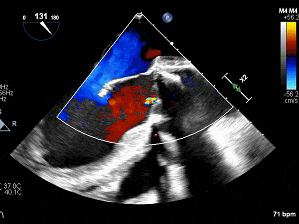

术后主动脉瓣生物瓣微量反流

(食道中段主动脉瓣长轴切面)